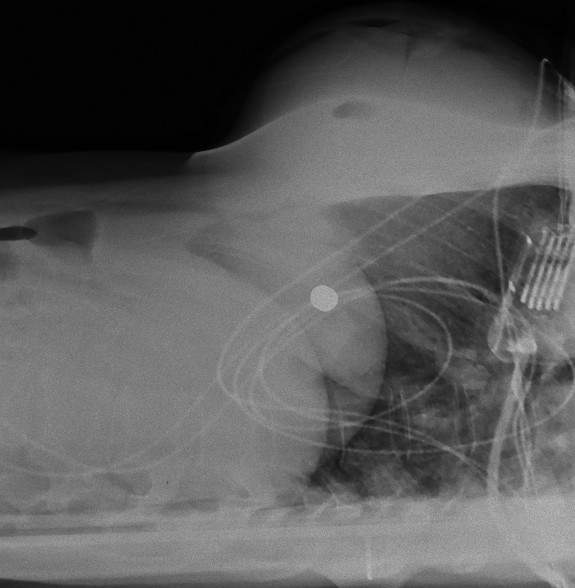

首先這真實案例好像發生在2018年,在一起槍擊案中一名女子的左胸中槍,隨後這名女子趕緊被送往醫院治療,想不到經救治之後發現子彈在矽膠中轉彎,沒打中重要部位幸而保住一命,而這起奇蹟的事件也被列入醫學文獻的研究案例之中

不過子彈打進矽膠中沒造成重大損傷還轉彎?外科醫師表示子彈從左胸進入,如果子彈沒轉彎可能會傷及肺跟心臟,但子彈打中矽膠後竟然改變了軌道,轉往女子的右乳房,結果只是彈出來一點撞斷女子的右側肋骨,最終結果就是胸部填充的矽膠損壞,肋骨破裂其它都是輕傷,相當不幸中的大幸